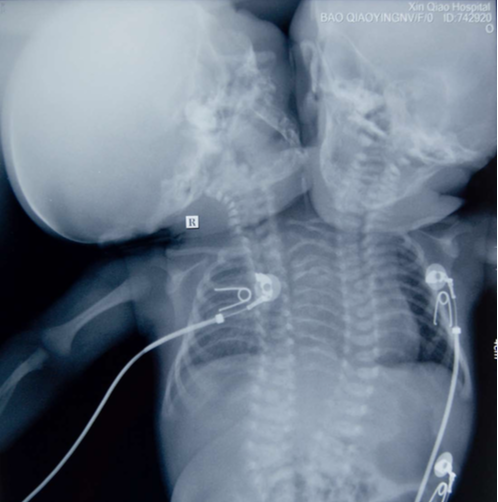

这天是2011年6月15日。重庆新桥医院,一对双头连体女婴已经存活了41天。此前,双头连体婴儿的存活纪录是11天,1996年由美国俄亥俄州的哥伦布儿童医院创造。

他们遇上的是医学上的小概率事件。受精卵在母体内如果正常分裂,产妇就会生下正常的分体双胞胎,一旦发生不完全分裂,连体双胞胎就会诞生。两个胎儿具有相同的染色体核型、性别、血型、毛发颜色、指纹。连体双胞胎各不相同,医学界大致分为头颅连胎、胸腹连胎、侧连胎、脊柱连胎等多种。但是廖国军的孩子更为罕见。从外观上看,婴儿从肩部往上生出了两个脑袋,但是只有一个身躯,一对左右手,一双左右脚。

“她们算一个?还是两个?”廖国军问。大夫答复,根据两根脊柱、两根食管、两个胃、两个肺的检查结果,可以肯定,双头婴是两个孩子,只是连体畸形的程度太重,以至于两个躯干融为一体,如同一个人。

遂宁市中心医院妇产科主任何佳说,刺激这对婴儿左边身体,左边的脑袋会动;刺激右边身体时,右边的脑袋会动,婴儿有一颗半心脏,共用右心房、右心室,分别有左心房、左心室。

5月10日,新桥医院对双头婴做了全面检查。结果显示,双头女婴有两个头颅、两套脊柱系统、两个食道、两个胃、两根气管、两个肺、两个肾脏、一个半心脏,共用躯干、胆囊、脾脏、骨盆、膀胱、生殖系统。两个头完整,颅骨发育基本正常,智力基本正常,左侧更好一些。由于两个头紧挨着,只要有一个头发出声音,另一个就会受到影响。

最后专家们都认为,严格说,双头女婴属于单体,而不是此前俗称的连体。

心脏只有一个半。正常的心脏四个心室四个心房,但是她们有三个心室三个心房,却支撑两个大脑、两套神经系统、一个完整身子,负担很重。而且有先天心脏病,房间隔、室间隔缺损。如果二氧化碳排不出来,会影响供氧,导致死亡。

虽然有两个肺,但是相邻的半个发育不好,肺不张。右边脑袋的只有右边管用,左边脑袋只有左边肺有用,中间的起到坏的作用,随时会因为炎症感染丧命。

神经支配系统协调很困难。左肺在吸的时候右肺在呼,一个在工作一个在休息,两个脑袋总是休息不了。脑子和心脏都累。协调性要经过很长时间磨合才能达到,但她们活到协调一致的希望渺茫。

即便双头婴能够存活下来,随着身高、体重的增加,心脏等脏器功能将无法承受越来越大的负担。同时,为保证她们存活下去,将要面对的费用无法估量。一个医生表示,“长期存活的希望很渺茫。迟早要解剖的。”